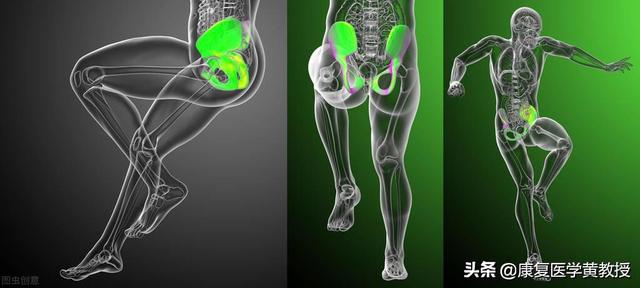

Les femmes jouent le rôle de reproductrices, le bassin des femmes est donc relativement plus large que celui des hommes, ce qui entraîne également certaines anomalies dans la ligne de force de l'articulation du genou, que nous mettons généralement sur le compte de la ligne de force de l'articulation du genou.L'angle où la ligne entre le point médian de la rotule et la tubérosité tibiale croise la ligne d'appui de la traction du quadriceps s'appelle l'angle q.L'angle q normal est de 10 à 15° chez l'homme et de 12 à 18° chez la femme. Plus l'angle q est grand, plus la rotule a tendance à se déplacer latéralement. Plus l'angle q est grand, plus la rotule a tendance à se déplacer latéralement. Plus l'angle de flambage est grand chez les femmes, plus le frottement entre la rotule et son fémur postérieur est important pendant l'accroupissement, ce qui explique pourquoi de nombreuses femmes sont très sujettes aux douleurs fémoro-patellaires latérales.

Bien qu'il puisse sembler à tout le monde que l'angle q chez les femmes n'est que de 3° supérieur à celui des hommes, ces 3° d'anomalie pour la délicate articulation du genou suffisent à rendre les femmes sujettes à des douleurs au genou, sachant que dans laUne déviation de 1° lors d'une chirurgie de remplacement du genou peut avoir des conséquences irréversibles。

La structure des hommes et des femmes est très différente

Nos ancêtres ont commencé à vivre en groupes et à répartir les tâches, les hommes devaient beaucoup chasser, ils ont donc développé un corps grand, des jambes fortes, des bras forts, tout cela pour se battre avec les bêtes et chasser, et les femmes, pour donner naissance, allaiter, pour maintenir la survie de la famille, ont commencé à développer la capacité de cueillir, et ont également commencé à développer la capacité de stocker les graisses dans le corps, tout cela pour se préparer à la reproduction de la progéniture. Les différences entre les hommes et les femmes à cette époque se sont accrues en raison des différents objectifs de survie.